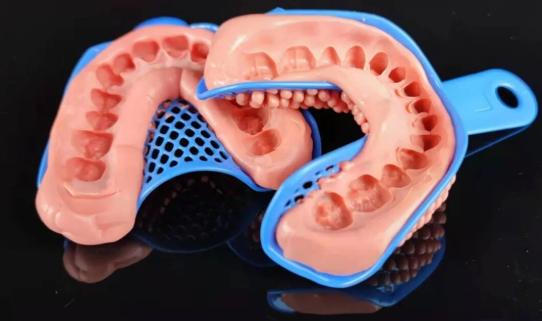

In dental impression making, silicone rubber offers high strength, excellent elasticity, good plasticity, stable dimensions, and high precision, providing crucial support for creating precise impressions.

In denture restoration, silicone rubber as a soft lining material can buffer occlusal force, improve occlusal pain and improve the fit between the denture base and the alveolar ridge.